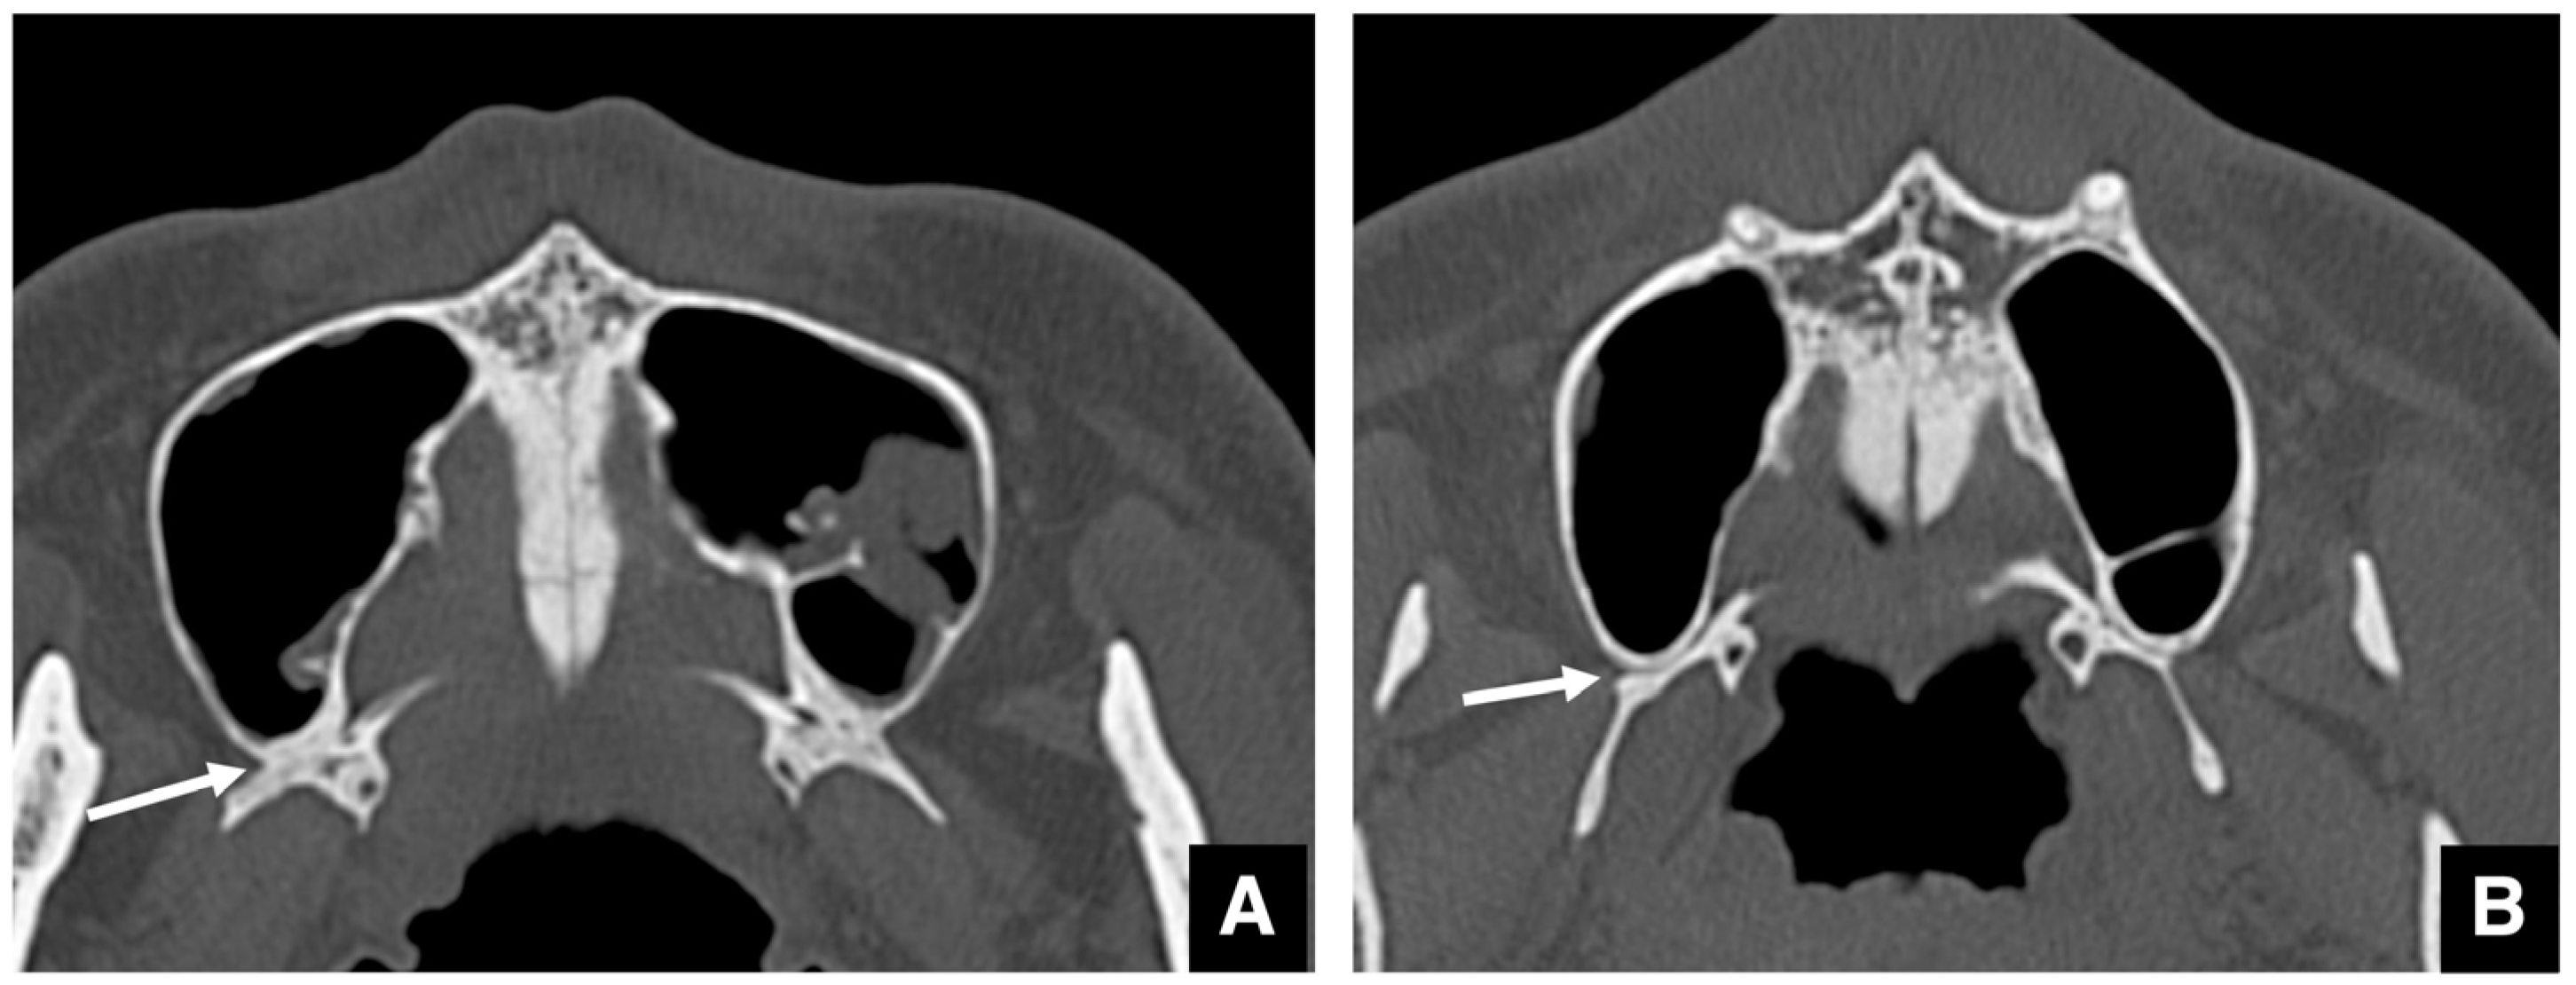

| Setting the osteotomy line 1. Evaluation of the position of the mandibular canal and surrounding bone quality Presence or absence of mandibular canal bifurcation and course of resection site Distance from the buccal wall of the mandibular canal to the buccal cortical bone margin Bone quality around the mandibular canal (CT number) 2. Distance from the mandibular notch to the lingula Whether it is 14 mm or more 3. Morphology of the mandible and variation in cortical bone thickness Cortical bone thickness in the medial osteotomy area and lateral osteotomy area Enhanced safety through improved visibility 1. Medial curvature of the mandibular ramus Mandibular ramus is straight or strong curvature 2. Course of small blood vessels along the bone surface Depression of the buccal-lingual cortical bone from the mandibular fossa to the mandibular ramus region, trabecular bone defect Improved success rates through enhanced postoperative bone integration 1. Degree of interference between bone segments The presence or absence of interference between the proximal and distal bone segments formed during virtual mandibular deformity surgery |